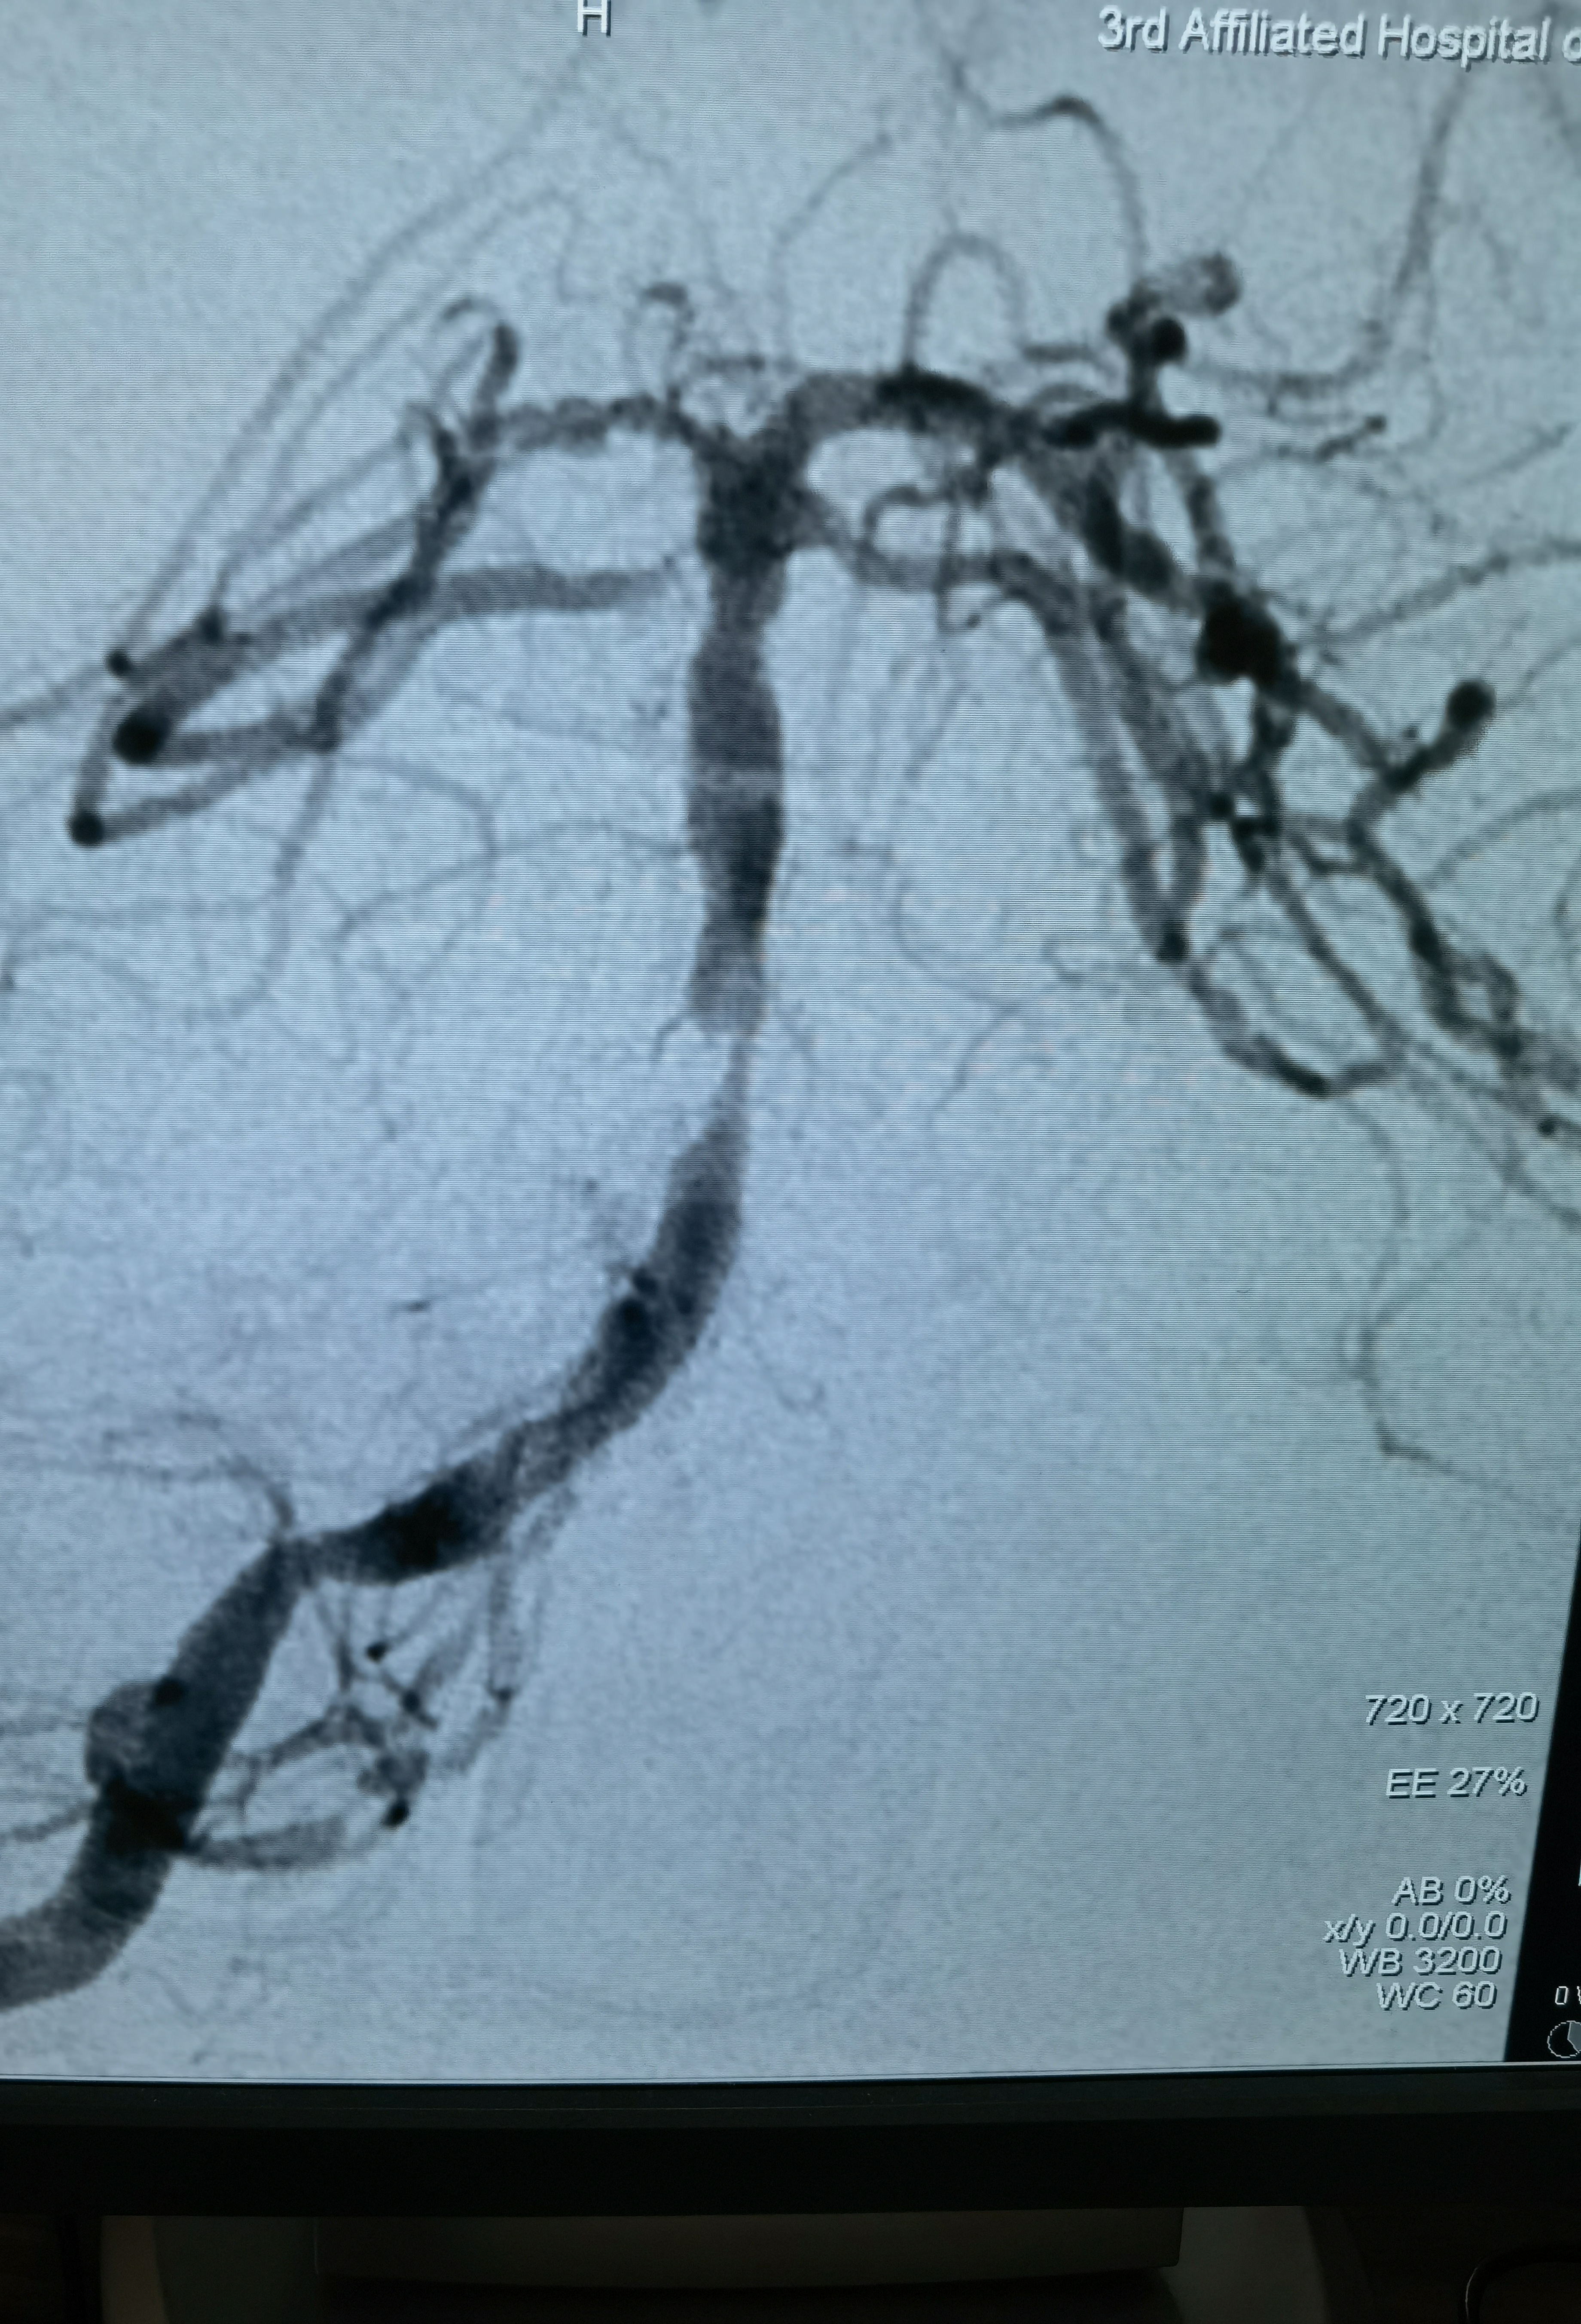

正位造影

狭窄85%